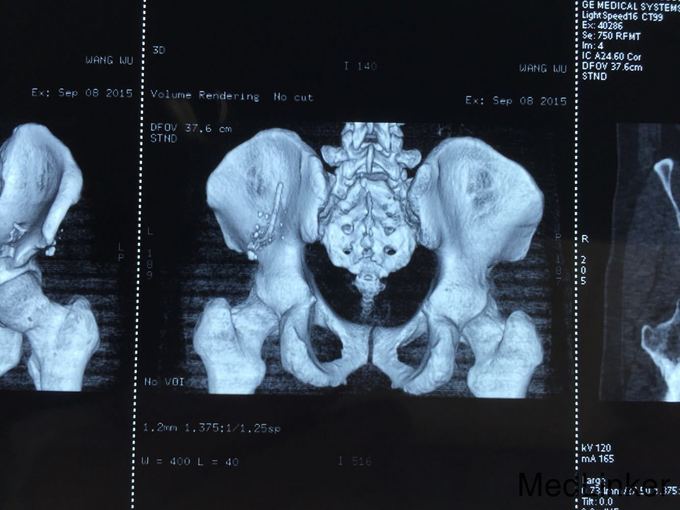

查体:T:36.6℃,P:80次/分,R:19次/分,Bp:130/85mmHg。心肺未见明显异常,腹平坦,无腹壁静脉曲张,腹部柔软,无压痛、反跳痛,腹部无包块,左侧腰髂部近左臀部可见钢筋样异物刺入直达左下腹腹壁皮下,未穿透腹壁皮肤,左臀部皮肤裂伤伴出血,伤口处压痛,肝脾肋下未触及,左下腹压痛,Murphy氏征阴性,移动性浊音阴性,肝脾肾区无叩击痛,肠鸣音未见异常。 辅助检查:全腹部CT检查示:1.盆腔见条状金属致密物,从左臀穿向前下腹部皮下,长约28cm;2.左侧腹膜周围见少许渗出性改变;3.左侧精索肿胀,其内气体影,左侧睾丸肿胀;4.左侧髂骨骨折。

诊断: 左侧腰骶部开放性损伤:左侧腰髂部盲管伤,腹膜后血肿,左侧精索静脉损伤,左侧髂骨骨折。 诊疗过程:入院后积极完善术前检查,无绝对手术禁忌,予以急诊行剖腹探查手术:左下腹乙状结肠外侧部位可见腹膜后血肿形成,初步判断钢筋样异物经左侧骶髂关节部位刺入至左下腹腹膜后部位后再经由壁腹膜外位至左下腹壁,遂决定行腹膜后血肿探查清除手术:于乙状结肠外侧后腹膜血肿部位打开后腹膜并清除积血,探查见左侧髂血管未见外伤性改变,探查见左侧精索静脉断裂伴出血,予以细线结扎,左侧输尿管、左肾、膀胱未见外伤性改变。冲洗腹腔干净,继续探查判断左下腹钢筋样异物均位于腹膜外位且未伤及重要器官,遂经腹壁侧予以拔出,查腹腔无活动性出血,,于左下腹腔术区置橡皮引流管一条经左侧腹壁引出,逐层缝合关闭腹腔,随后行臀部外伤扩创术。术后患者恢复佳,顺利出院。